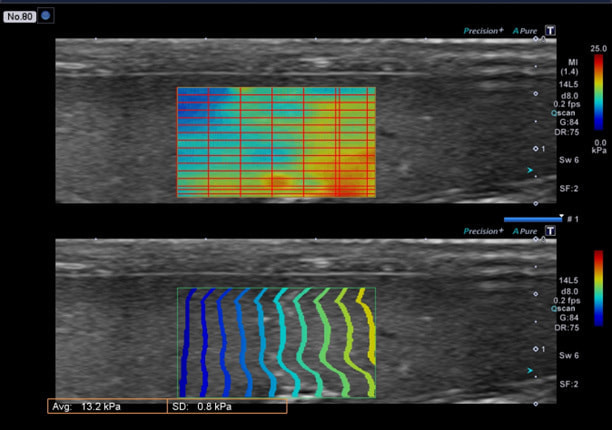

肝硬度測定機能付きエコー (Shear Wave Elastography)

せん断波という波を発生させ、肝臓での伝播速度を元に”硬さ”を数値などで表示します。

肝機能異常のイメージ

(Canon HP、Aplio Verifiaより引用)